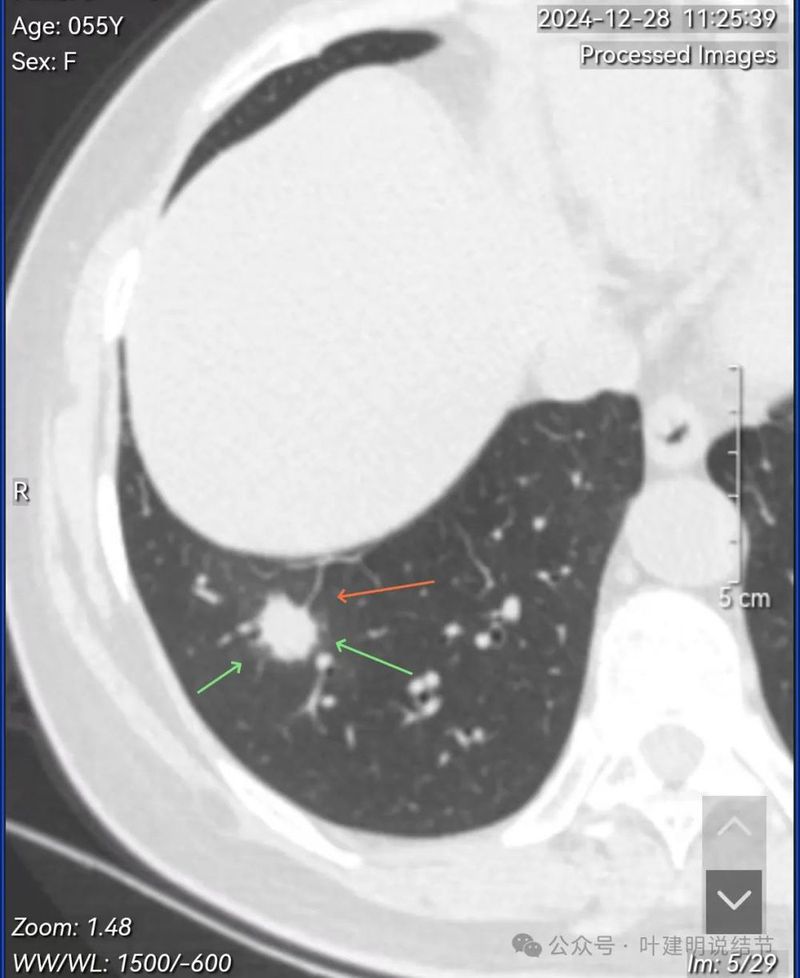

再看在我门诊时2025年1月14号复查的靶扫描影像:

非薄层上见病灶混合密度,整体轮廓较清。

明显的血管进入与异常增粗。

灶内密度杂乱,血管进入与增粗,表面不平。

实性成分明显,但缺乏收缩力;边上是磨玻璃成分,整体轮廓较清;邻近血管走行,但没有形成血管弯征。